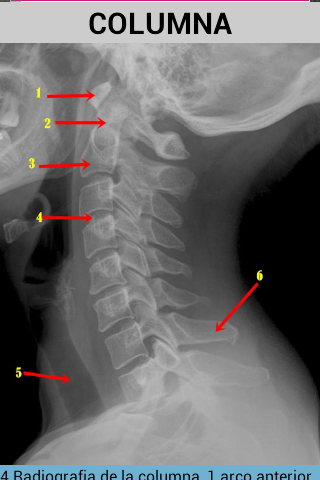

Tato aplikace se naučí snadno identifikovat anatomické struktury, které lze vidět v radiologii.obsahuje obrázky prostých rentgenových snímků, MRI a CT skenů.

Také s každým obrázkem je vysvětlení, které lépe porozumí.

obsahuje obrázky hlavy, páteře a hrudníku.